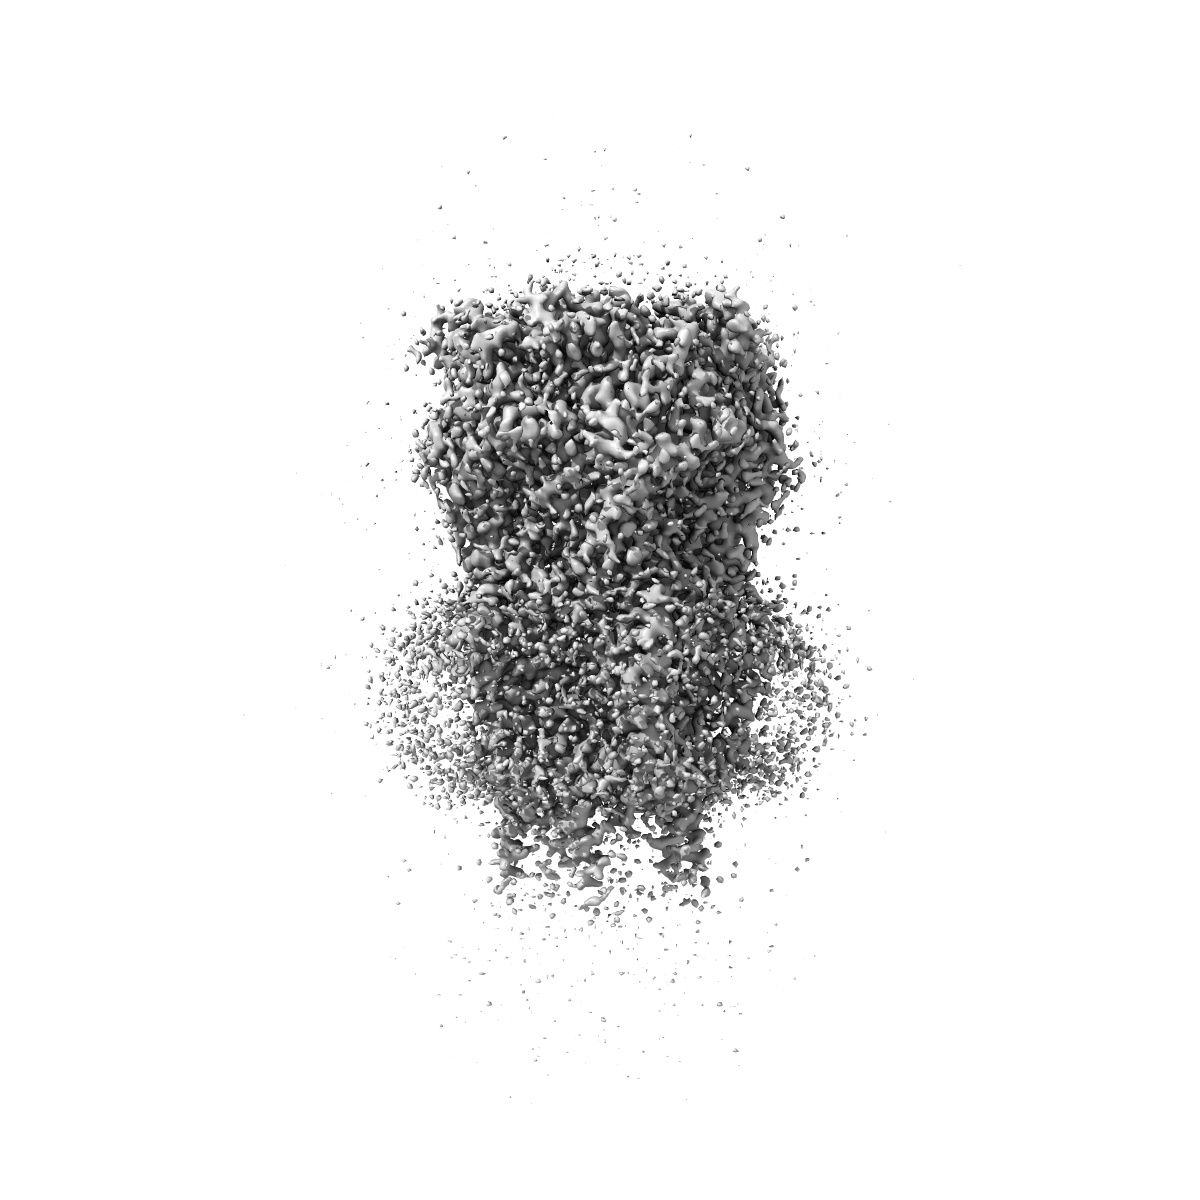

CryoEM structure of human rho1 GABAA receptor in complex with (R)-GABOB in the desensitized state

Sample: human rho1 GABAA receptor

Cryo-EM structures of rho 1 GABA A receptors with antagonist and agonist drugs.

Fan C , Cowgill J , Howard RJ , Lindahl E

(2025) Nat Commun , 16 , 7077 - 7077